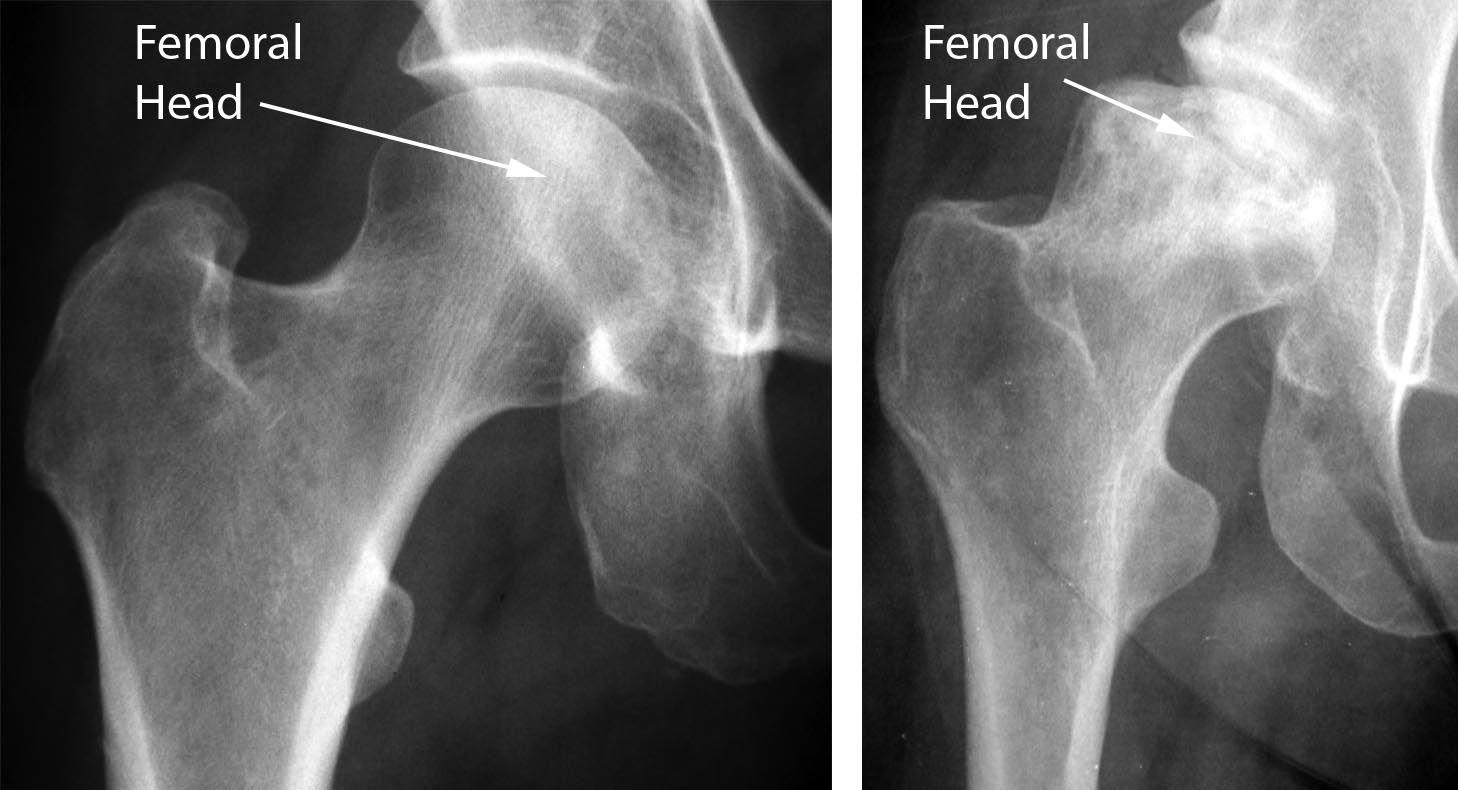

X 射线。 X 射线提供致密结构的图像,例如骨骼。X 射线用于确定股骨头中的骨头是否塌陷以及塌陷到什么程度。

(左) 健康髋关节的 X 光片。 (右) 在这张 X 光片中,骨坏死已发展为股骨头塌陷。

骨坏死通常被视为楔形区域,在股骨头的上外侧部分具有致密的白色硬化边界。在侧视图中,通常可以在股骨头表面下方看到一条称为“新月征”的透明线。